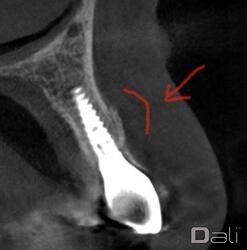

Following a GBR at the time of implant placement, a buccal ridge deficiency persisted. Surgical uncovery of the implant to expose the cover screw revealed successful bone regeneration around the implant, but a residual lack of ridge contour. Instead of using a traditional particulate graft covered with a resorbable membrane, a “flexible bone graft” sheet, DALI Flex Graft, was placed over the buccal plate to augment the buccal contour. Because the graft comes hydrated, it is easy to handle and adapt to the defect location. The flap was then pulled over the graft and adapted around the healing abutment. Following 6 weeks of healing, we see nice healing and an obvious increase in the facial contour.